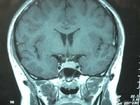

腦垂體為重要的內分泌器官,內含數種內分泌細胞,分泌多種內分泌素,如果某一內分泌細胞生長腺瘤,則可發生特殊的臨床表現。其詳細情況分別敘述如下:

視力視野障礙

早期垂體腺瘤常無視力視野障礙。如腫瘤長大,向上伸展,壓迫視交叉,則出現視野缺損,外上象限首先受影響,紅視野最先表現出來。以後病變增大,壓迫較重,則白視野也受影響,漸漸缺損可擴大至雙顳側偏盲。如果未及時治療,視野缺損可再擴大,並且視力也有減退,以致全盲。因為垂體瘤多為良性,初期病變可持續相當時間,待病情嚴重時,視力視野障礙可突然加劇,如果腫瘤偏於一側,可致單眼偏盲或失明。

如果垂體瘤向後上生長壓迫垂體柄或下丘腦,可致多飲多尿;如果腫瘤向側方生長侵犯海綿竇壁,則出現動眼神經或外展神經麻痹;如果腫瘤穿過鞍隔再向上生長致額葉腹側部,有時出現精神症狀;如果腫瘤向後上生長阻塞第三腦室前部和室間孔,則出現頭痛嘔吐等顱內壓增高症狀;如果腫瘤向後生長,可壓迫腦幹致昏迷、癱瘓或去大腦強直等。